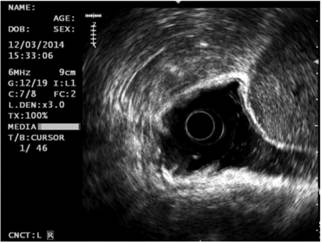

Teniendo en cuenta los hallazgos endoscópicos, se decidió ampliar el estudio a través de una ultrasonografía endoscópica gástrica, la cual mostró en el cuerpo una lesión elevada de 20 mm hipoecoica que infiltraba la mucosa y parcialmente la submucosa, en el antro hubo otra lesión subepitelial, la cual dependía de la muscular propia de 60 mm de diámetro con espacios quísticos en su interior (Figura 2). No se encontraron adenopatías perilesionales o en el tronco celíaco, se realizó el diagnóstico de CG temprano y GIST en la cuarta capa. La biopsia tomada a la lesión del cuerpo gástrico confirmó la presencia de un adenocarcinoma gástrico moderadamente diferenciado. Se realizó un TAC abdominal contrastado y se evidenció únicamente que en el GIST no había metástasis.